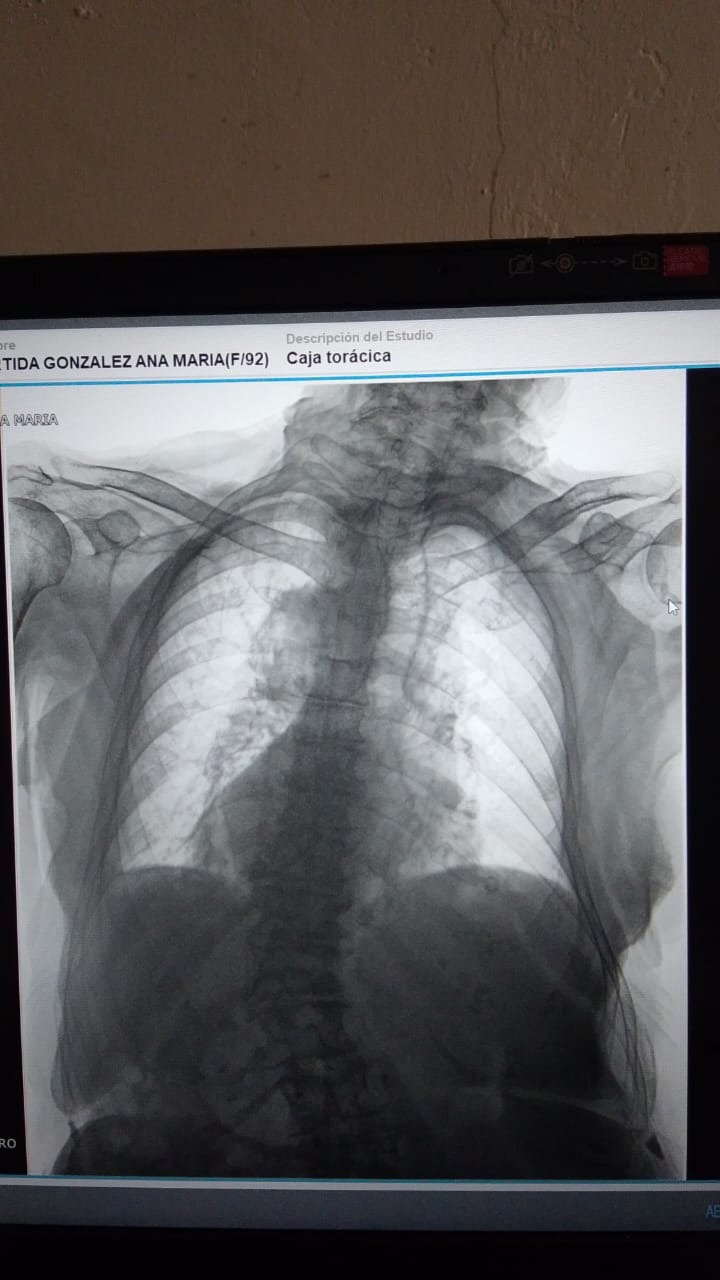

A lo largo de mi enfermedad he sufrido diferentes accidentes por las caidas, he estado en quierofano varias ocaciones. Hace unos dias mi salud se deterrioro mis pulmones estan dañados, los Doctores me dignosticaron Efisema pulmonar, y neumonia. Hoy estoy conectada a un tanque de oxígeno 24 horas del día, Es difícil cubrir los gastos de mi enfermedad entre medicamentos, pañales, y cuidados.